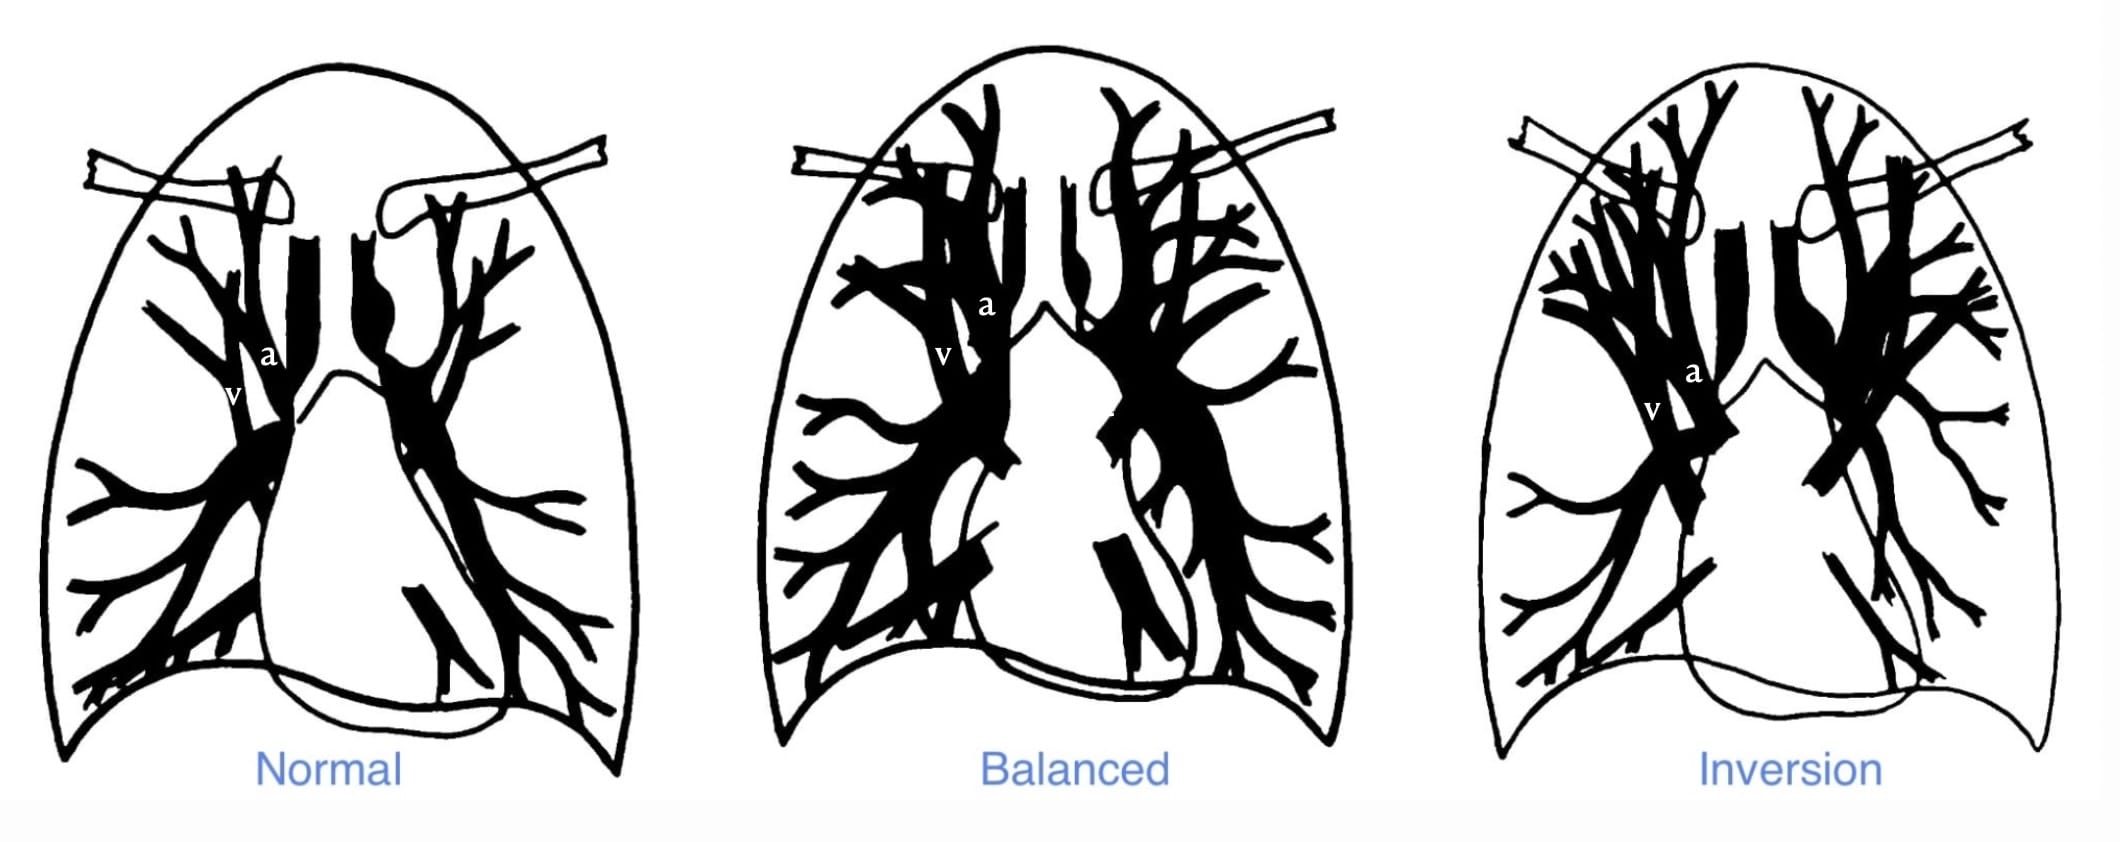

The distribution of pulmonary blood flow.

In the physiologic state, reflective of cranial-caudal hydrostatic pressure, the vessels—arteries and veins—in the lower lungs are slightly more distended than those in the upper lungs.

When pulmonary blood flow and volume is increased, as in a left-to-right shunt or hypervolemia, the vessels are distended, and equal in caliber from top to bottom.

In chronic—not acute—pulmonary venous hypertension, the upper zone vessels are more distended. This occurs because of pathologic changes—intimal hypertrophy and hyperplasia—that develop predominantly in these vessels over years. The resultant increase in regional vascular resistance results in the redistribution of blood flow.

Source: Milne, et al. The radiologic distinction of cardiogenic and noncardiogenic edema

Hydrostatic Lung Edema and Thoracic Vessels

The distribution of pulmonary blood flow.